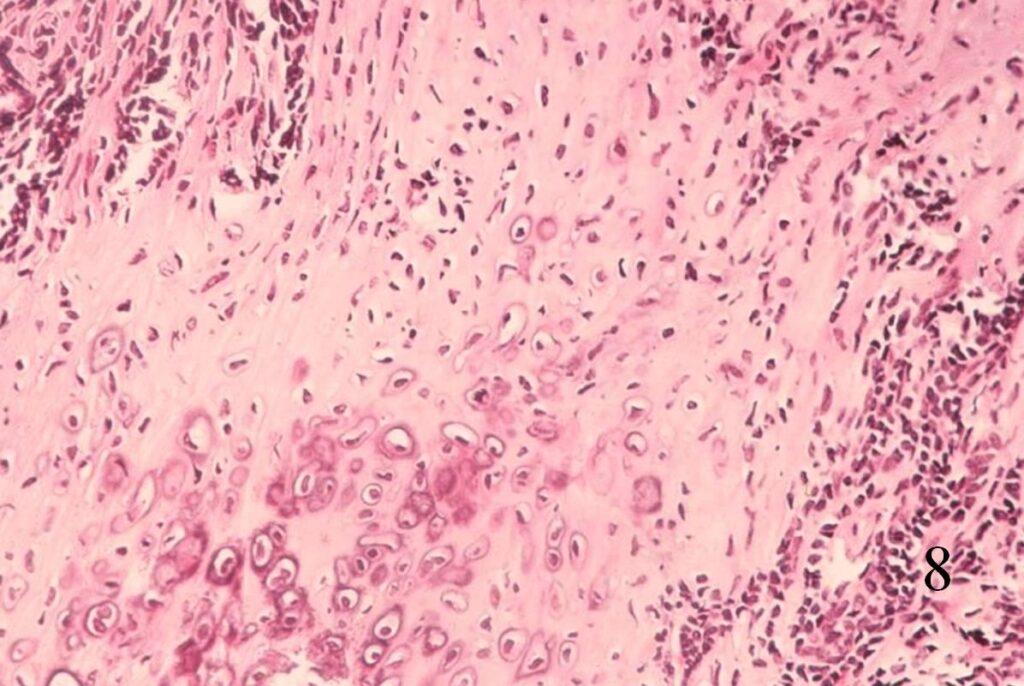

Extraskeletal Mesenchymal Chondrosarcoma (Fig. 8-10)

• Abundant small round blue cells

• Undifferentiated

• Round to elongate or spindle nuclei

• May grow in sheets or nodules, surround by fibrous tissue

• Usually proliferate around narrow vessels and pericytic sinusoidal vessels

• Islands of cartilage, may be calcified or ossified

Fig. 8

Fig. 9

Fig. 10

Fig. 8-10 Low (Fig. 8) and high power (Fig. 9) magnification of a mesenchymal chondrosarcoma shows cartilaginous areas and a mesenchymal component.